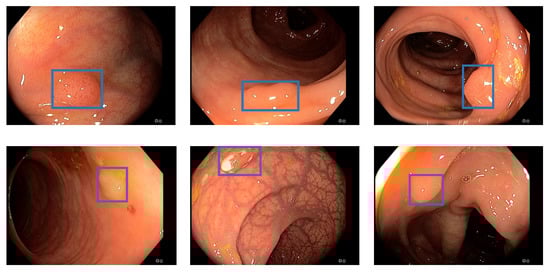

3.2. EndoData Evaluation

Our own validation set (EndoData) allows us to detect polyps more precisely and accurately. Table 8 shows an overview of the videos in the dataset and Figure 13 shows examples of the dataset. The EndoData dataset records sequences as the polyp appears in the scene. Therefore, polyps are marked precisely with their first appearance. In comparison, the polyp sequence of the CVC-VideoClinicDB dataset might not start when the polyp is already detected. Those early seconds are crucial as the gastroenterologist has to identify and not miss the polyp during this time. If the polyp is not detected in the early sequence, it increases the risk of missing it. As we like to focus on this early detection, we introduce a second metric that can just be evaluated with a dataset like ours. This metric marks the seconds from first seeing the polyp to first detecting the polyp. We call it first detection time (FDT). Additionally, we compute the FPs and the false positive rate (FPR) per video (Table 10 and Table 11).